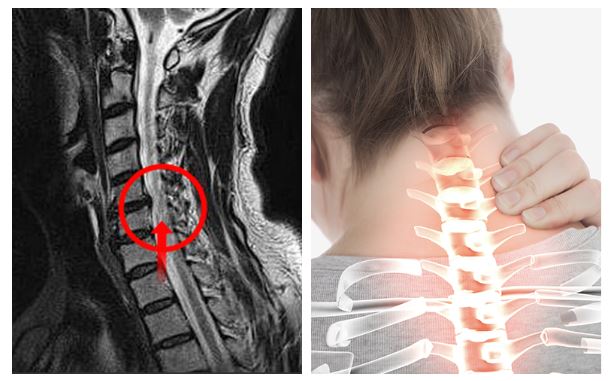

목디스크는 목 쪽 척추인 경추와 경추 사이에 위치한 추간판 사이로 내부의 수핵이 빠져나와서 신경근 또는 척수를 누르는 질환이며 목디스크의 정확한 명칭은 경추 추간판 탈출증이라고 합니다. 잦은 휴대폰 사용과 함께 업무를 볼 때 자연스럽게 구부정한 자세로 앉아 있다 보니 이로 인해 목디스크 증상까지 동반되는 경우가 많다고 합니다. 목디스크는 오랜 시간 축척된 경추 관절 및 디스크의 퇴행성 변화가 원인입니다.

목디스크를 치료하기 위해서는 무엇보다도 전문 병원에서의 현재 상태에 대한 정확한 진단이 필요합니다. 위에서 설명드렸다시피 본인이 어떤 원인으로 인한 목디스크 증상을 겪고 있는지에 대해서도 확인이 필요하며, 나아가 현재 디스크가 경추 사이에서 탈출되면서 어느 정도로 신경 부위를 압박하고 있는지 그 수위에 대한 확인도 매우 중요합니다.

하지만 비수술적 치료를 통해서 증상이 개선되지 않거나 혹은 목디스크 진행 단계가 심각하게 진행되어 있는 경우에는 곧바로 수술을 통하여 치료가 진행됩니다. 연성 디스크일 경우에는 후방접근법, 경성 디스크일 경우에는 전방 접근법으로 수술이 진행되며 이 두 방법 모두 경추부 디스크를 확인하기 위하여 목 부분 절개를 해야 하므로 전신마취를 해야 한다는 단점이 있습니다. 따라서 최근에는 전신마취 없이 목 부위를 약 1cm 정도만 절개하여 진행하는 내시경 미세 감압 수술 기술이 개발되어 수술 과정에 의한 사고 예방과 함께 환자의 수술 후 빠른 회복도 가능하다고 합니다.